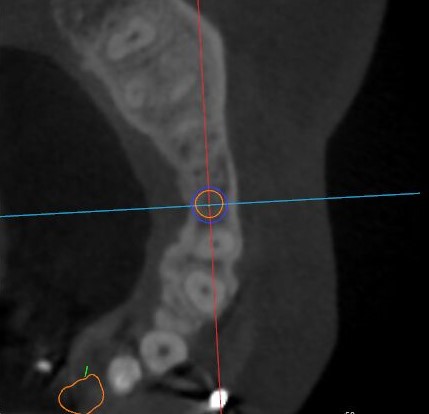

冠狀面視圖

矢狀面視圖

軸狀面視圖

三維視圖

根據(jù)患者CT顯示,使用種植導(dǎo)航軟件設(shè)術(shù)前手術(shù)方案??紤]到患者拒絕手術(shù)摘除上頜竇囊腫等因素,此次手術(shù)選用了Straumann骨水平4.10*8.0mm的植體,植體末端位點設(shè)計距上頜竇底壁2mm處的同時兼顧種植方向和修復(fù)間隙,來達(dá)到理想的效果。